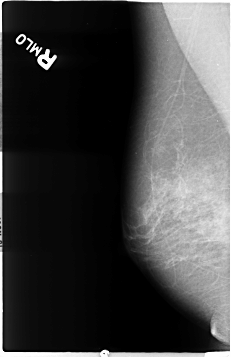

B_3038_1.RIGHT_MLO

RIGHT_MLO LINES 4640 PIXELS_PER_LINE 3000 BITS_PER_PIXEL 12 RESOLUTION 50 NON_OVERLAY